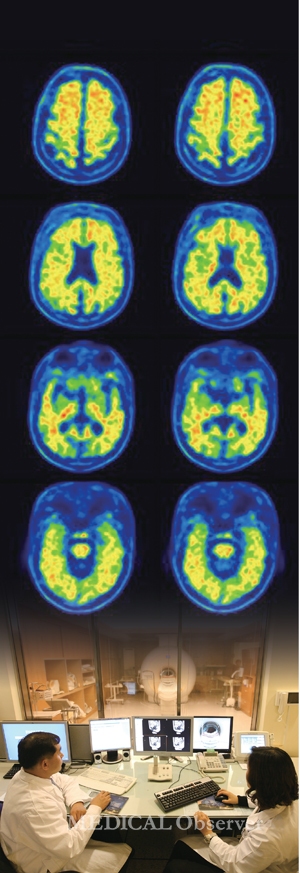

우울증·조현병 관련 연구 활발…진단 정확도 높게 나와

우울증은 변연계(limbic system)와 전두엽(prefrontal cortex) 영역에서 이상이 생겨 불면증, 식욕저하, 감정 기복 등 각종 우울 증상이 발병한다고 알려졌다. 따라서 fMRI 등을 이용한 뇌영상 연구가 활발한 영역이다.

2008년 호주 알프레드 정신질환 연구소 Fitzgerald PB 박사팀에 따르면 우울 증상을 보이는 환자의 표정을 촬영한 fMRI 뇌영상을 분석한 결과, 영상 촬영만으로 우울증을 최대 84%까지 진단했다.

뇌의 휴지기(resting-state)에도 fMRI 영상을 통해 우울증 진단 여부가 가능한지 알아보는 시험도 눈에 띈다.

연구에 참여한 대상군이 쉬는 동안 이들의 표정 등을 분석해 우울증 동반 여부를 진단했는데 결과는 긍정적이었다. 정확도가 95%까지 나올 만큼 우울증 환자를 거의 정확하게 구별한 것(Zeng LL et al. 2012, Brain 135(Pt 5)).

연구팀은 2014년에도 추가 결과를 도출하기 위해 뇌의 휴지기에 fMRI를 이용해 뇌영상기술로 우울증 진단 여부가 가능한지 알아봤다. 결과는 이전 연구와 비슷한 93%의 정확도로 우울증을 진단했다(Zeng LL et al. 2014 Hum Brain Mapp 35(4)).

조현병은 우울증보다 뇌영상 연구가 더욱 보편화됐다.

대표적으로 2002년 미국 다트머스 컬리지 James C Ford 박사팀이 fMRI 뇌영상을 이용해 조현병 환자와 정상인을 구분할 수 있는지 알아봤다. 그 결과 조현병 환자는 정상인보다 회백질 용적은 물론 해마 역시 감소돼 있어, 구조적 결함을 넘어 기능적 이상도 동시에 보인다는 점을 확인했다. 정확도는 87%였다.